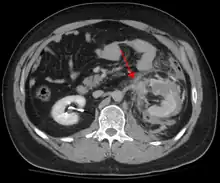

Blunt abdominal trauma

Blunt abdominal trauma (BAT) represents 75% of all blunt trauma and is the most common example of this injury.[3] 75% of BAT occurs in motor vehicle crashes,[4] in which rapid deceleration may propel the driver into the steering wheel, dashboard, or seatbelt,[5] causing contusions in less serious cases, or rupture of internal organs from briefly increased intraluminal pressure in the more serious, depending on the force applied. Initially, there may be few indications that serious internal abdominal injury has occurred, making assessment more challenging and requiring a high degree of clinical suspicion.[6]

There are two basic physical mechanisms at play with the potential of injury to intra-abdominal organs: compression and deceleration.[7] The former occurs from a direct blow, such as a punch, or compression against a non-yielding object such as a seat belt or steering column. This force may deform a hollow organ, increasing its intraluminal or internal pressure and possibly lead to rupture.

Deceleration, on the other hand, causes stretching and shearing at the points where mobile contents in the abdomen, like bowel, are anchored. This can cause tearing of the mesentery of the bowel and injury to the blood vessels that travel within the mesentery. Classic examples of these mechanisms are a hepatic tear along the ligamentum teres and injuries to the renal arteries.

When blunt abdominal trauma is complicated by 'internal injury,' the liver and spleen (see blunt splenic trauma) are most frequently involved, followed by the small intestine.[8]